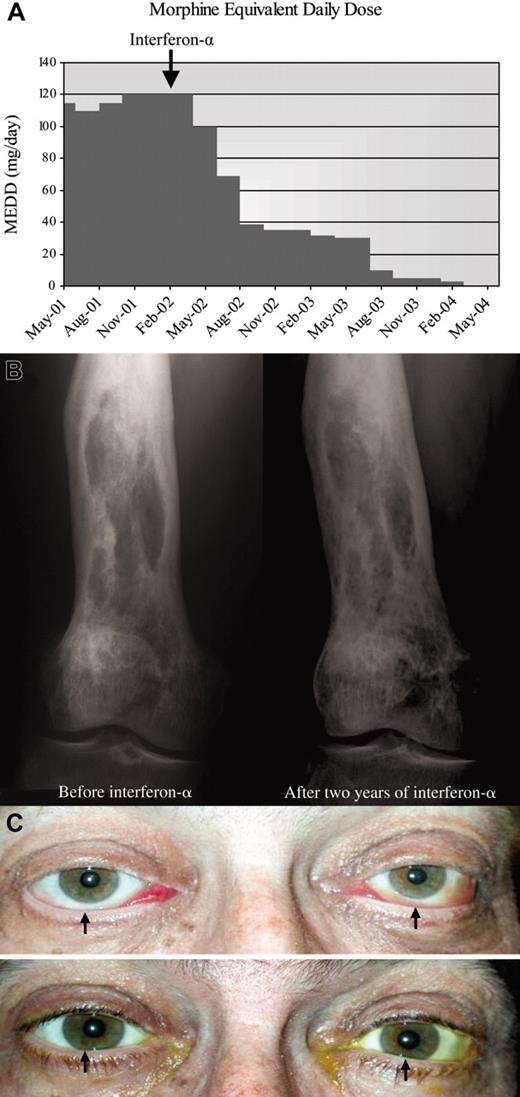

A 53-year-old man presented with a bilateral periorbital congestion, erythema, and proptosis. Exophthalmos was confirmed by Hertel exophthalmometry measurements of 27 mm. MRI scan of the orbit showed bilateral intraconal masses with increased signal on T2-weighted images.

Long bone radiographs revealed a localized area of fibrous sclerosis in the distal left fibula. Computed tomography scans of the abdomen demonstrated retroperitoneal fibrosis. Retro-orbital mass biopsy demonstrated Touton giant cells with CD68+, S100–, and CD1a– histiocytic infiltrate, confirming the diagnosis of Erdheim-Chester disease. The patient's visual acuity and exophthalmos worsened despite therapy with methotrexate, cyclophosphamide, etoposide, and high-dose prednisone and vincristine.

Interferon-α was started, but the initial dose of 6 × 106 units subcutaneous 3 times per week was reduced 6 months later to 3 × 106 units and 4 months afterward to 1 × 106 units because of fatigue. The patient tolerated low-dose interferon-α well and continued on it for an additional 16 months. Therapy was stopped because the patient's eye examination had normalized (Figure 2C). Eight months later, new skin lesions were noted, and biopsy confirmed relapse. Interferon-α was recently restarted, and the patient again demonstrated response.

Response to interferon-α in patients 2 and 3. (A) Morphine equivalent daily dose (MEDD; mg/d) needed to manage pain before and after interferon-α therapy. Patient required 120 mg/d opioids before starting interferon-α. After 2 years, he no longer needs opioids. (B) Bone radiograph of the right femur reveals mixed osteosclerotic and osteolytic lesions before treatment. Ongoing improvement is seen after 2 years of treatment with interferon-α. (C) (Top) Bilateral exophthalmos with chemosis, engorged conjunctival vessels, and inferior scleral show (arrows) at presentation. Loss of eyelashes because of recent chemotherapy is noted. (Bottom) Exophthalmos, chemosis, and inferior scleral show (arrows) resolved after 2 years of interferon-α. Eyelashes have grown back.